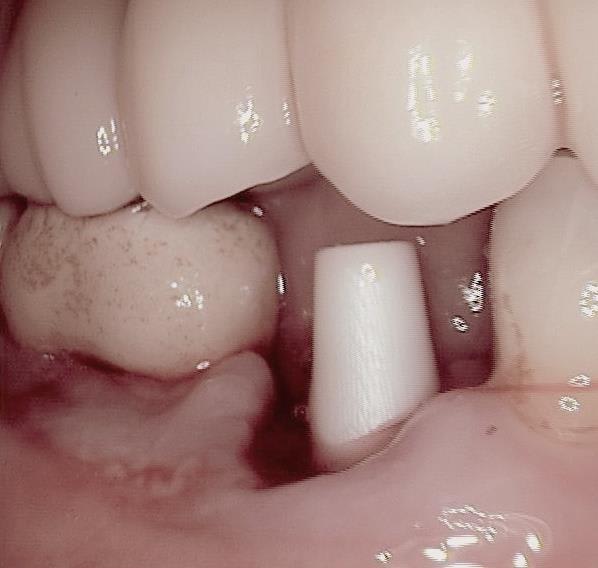

Pour ceux que ca interessent, et parce qu on a m a demandé des cas supplémentaires dans le sujet 23 implants rehabilitation totale, voici un autre cas d implantation immédiate avec la technique minimalement invasive et condensation grace aux forets.

Le patient a reçu un traitement il y a dix ans dans le maxillaire et dans le 4eme quadrant.Comme on peut le voir j´ai du extraire quelques dents au maxillaire: 35 37 et 45.

Le septum de la 37 a été foré avec un foret conique 3 faces.

J ai planté à 60 Ncm sans fracturer le septum.Juste après l opération , les prep caps en zircon ont été cémenté.La restauration définitive 34 jusqu` à 37 été fixé 2 semaines après l implantation avec implantlink (detax). Après un an, le bridge a été retiré facilement pour voir l´état de la gencive et faire une radio de contrôle.On la re ossifiction est satisfaisante et que la gencive "aime" le zircon.

Le bridge a ensuite été recémenté sans correction nécessaire du bridge.